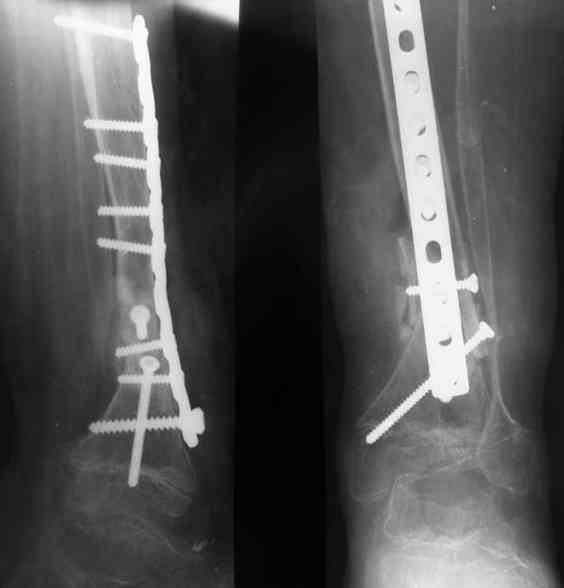

Уважаемые коллеги! В отделении на лечении наблюдается пациент 16 лет с диагнозом: Псевдоартроз костей левой голенив нижней трети. Вальгусная деформация обоих коленных суставов. Укорочение левой н/конечности11см. С 1997 года состоит на учёте у онколога с диагнозом: Рабдомиосаркома мышц тазового дна IV ст., с метастазами в метафизы берцовых костей.Проведена полихимиотерапия, лучевая терапия. В 1998 г. удаление опухоли. Послеоперационный период без особенностей. С 1998 года со стороны онкологии ремиссия, перестройка очагов метастазирования в берцовых костях по типу фиброзной дисплазии.В 1999 г. патологический перелом костей левой голени в н/трети. Лечение в гипсе 1.5 месяца, затем компрессионно-дистракционный остеосинтез апп. Илизарова. Сращения на месте псевдоартроза не достигнуто. С 1999г. ходит без нагрузки на левую н/конечность. Выраженный остеопороз костей н/конечностей. 17.11.05. Операция: Костная пластика зоны псевдоартроза левой б/берцовой кости по типу "русский замок", остеосинтез пластинкой и винтами. После начала нагрузки на конечность рецидив деформации, миграция фиксаторов. 05.12.06. Операция: Удаление фиксаторов из левой голени. Шарнирная остеотомия трети левой б/берцовой кости, остеотомия м/берцовой кости. Дистракционный остеосинтез апп. Илизарова. Устранены основные виды деформации б/берцовой кости. Планировали в дальнейшем несвободную костную аутопластику и интрамедуллярный остеосинтез с блокированием, но кость очень тонкая, склерозированная, выраженный остеопороз. Возникают большие сомнения о возможности сращения даже при этих условиях. Будем рады услышать ваши мнения по дальнейшему лечению данного пациента. Екатериан Анатольевна Озерова, детское отделение УНИИТО